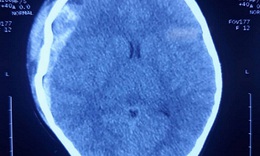

Y tế - 18/10/2025 13:14SKĐS - Trong lúc chơi một mình, bé 3 tuổi không may bị ngã cầu tháng dẫn đến vỡ xương sọ, tụ máu ngoài màng cứng. Phát hiện tình trạng bất thường, gia đình vội đưa trẻ đến bệnh viện thăm khám và may mắn được bác sĩ phẫu thuật thành công.